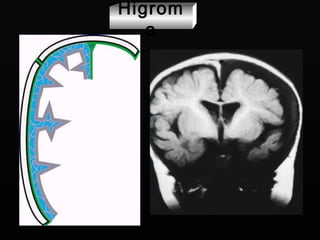

Higroma